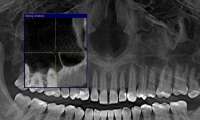

14734076948630.jpg (62Кб, 718x219)

Расскажите про расширяющие пластины. Насколько они дикцию портят? Насколько болезненно их устанавливать/носить? Есть какие-то альтернативы их установке?

Пикрилейтед мой диагноз. Прогнозируют 2-2.5 года ношения брекетов. Встанет все это в 150-200 штук. Это адекватная цена для моего случая?

Брекеты на обе челюсти + пластины, ну если ДС - думаю норм.